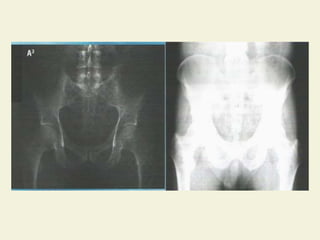

IMAGEM RADIOGRÁFICA

 Imagem produzida sobre uma

emulsão fotográfica

 Áreas escuras – radiotransparentes

 Áreas claras – radiopacas

IMAGEM RADIOGRÁFICA  Imagemproduzida sobre uma emulsão fotográfica  Áreas escuras – radiotransparentes  Áreas claras – radiopacas